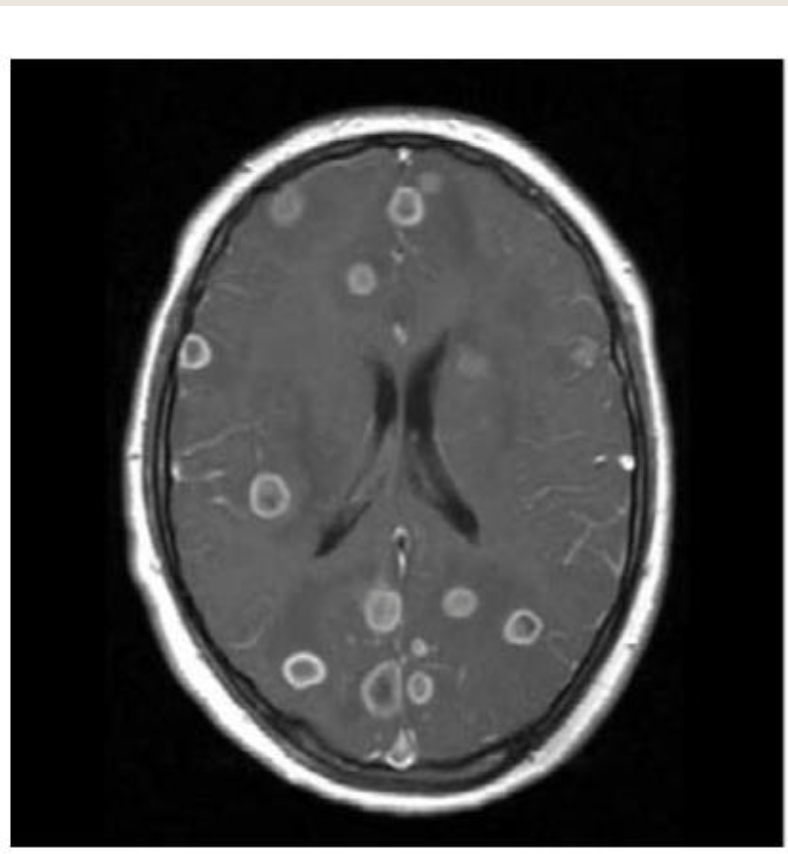

The commonest cause of this infection

What is Staph aureus